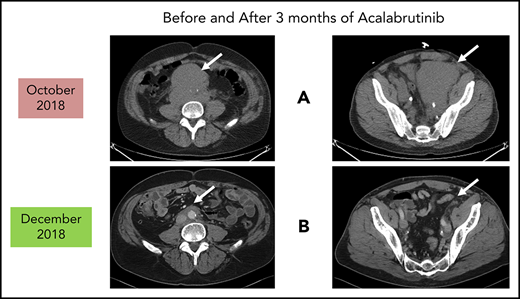

Before and after 3 months of acalabrutinib. A 54-year-old man was diagnosed with stage IVB MCL in 2014. He received chemoimmunotherapy including cytosine arabinoside and an adjuvant autologous SCT. (A) In 2018, he relapsed with left leg swelling due to bulky pelvic disease and a new deep vein thrombosis. (B) After biopsy proof of relapsed MCL, he received acalabrutinib 100 mg twice daily, rituximab, and apixaban; within 3 months, he achieved a marked response with no side effects of the combination. He has returned to full-time work and continues on therapy as of January 2019.

Patients who relapse are typically treated with salvage chemoimmunotherapy or other approved agents. These include the proteasome inhibitor bortezomib,13,14 the immunomodulatory agent lenalidomide,15-19 the mammalian target of rapamycin complex 1 inhibitor temsirolimus (Europe, not United States),20-24 and the Bruton tyrosine kinase (BTK) inhibitors discussed in the next section.25-29 The bcl-2 inhibitor venetoclax has orphan drug designation (but not approval) for MCL.30,31 Despite the plethora of agents for this disease, most patients will need all of them during their lifetime. Thus, there is always a need for additional agents as illustrated by the case described in Figure 1.